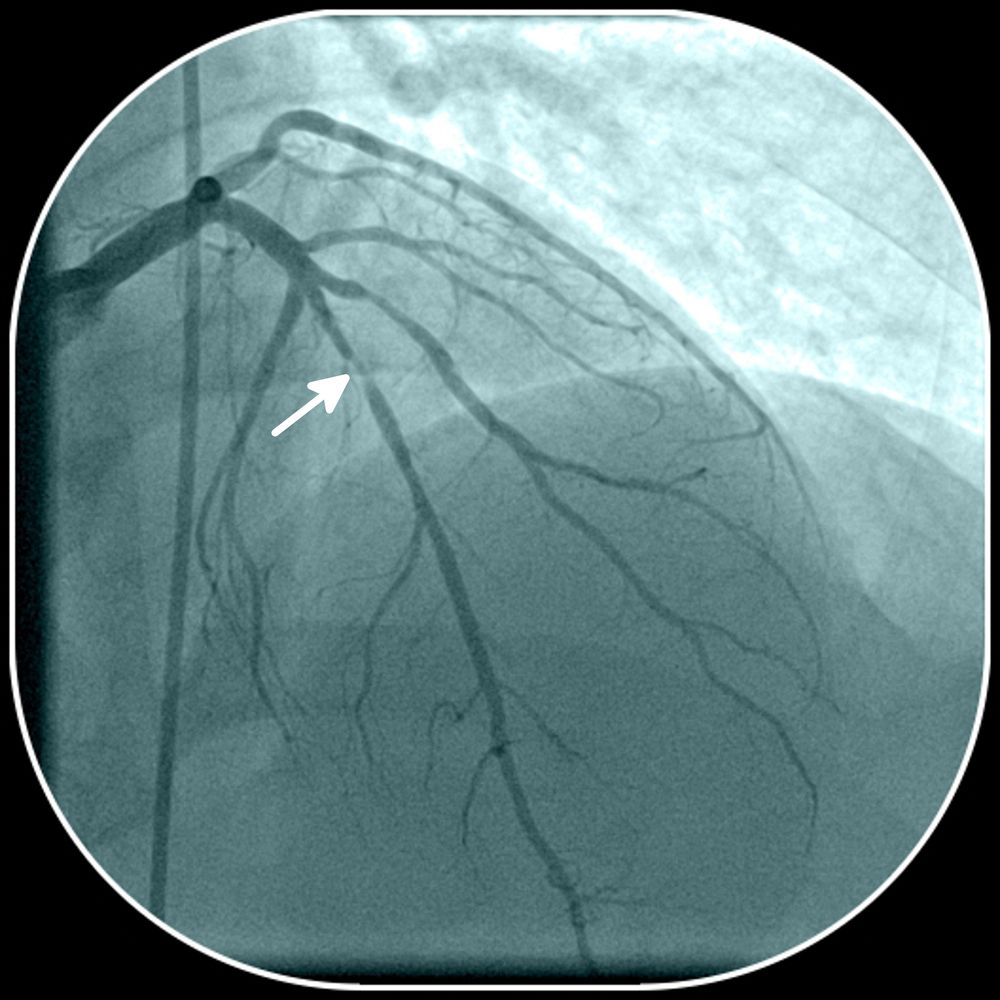

Coronary artery disease. ©kalewa/Shutterstock.com

Those with HIV infection and symptomatic CAD present at a younger age and experience a higher rate of post-angioplasty restenosis. Also, coronary artery plaques have been found to be more prevalent and extensive in HIV-infected men, they noted.